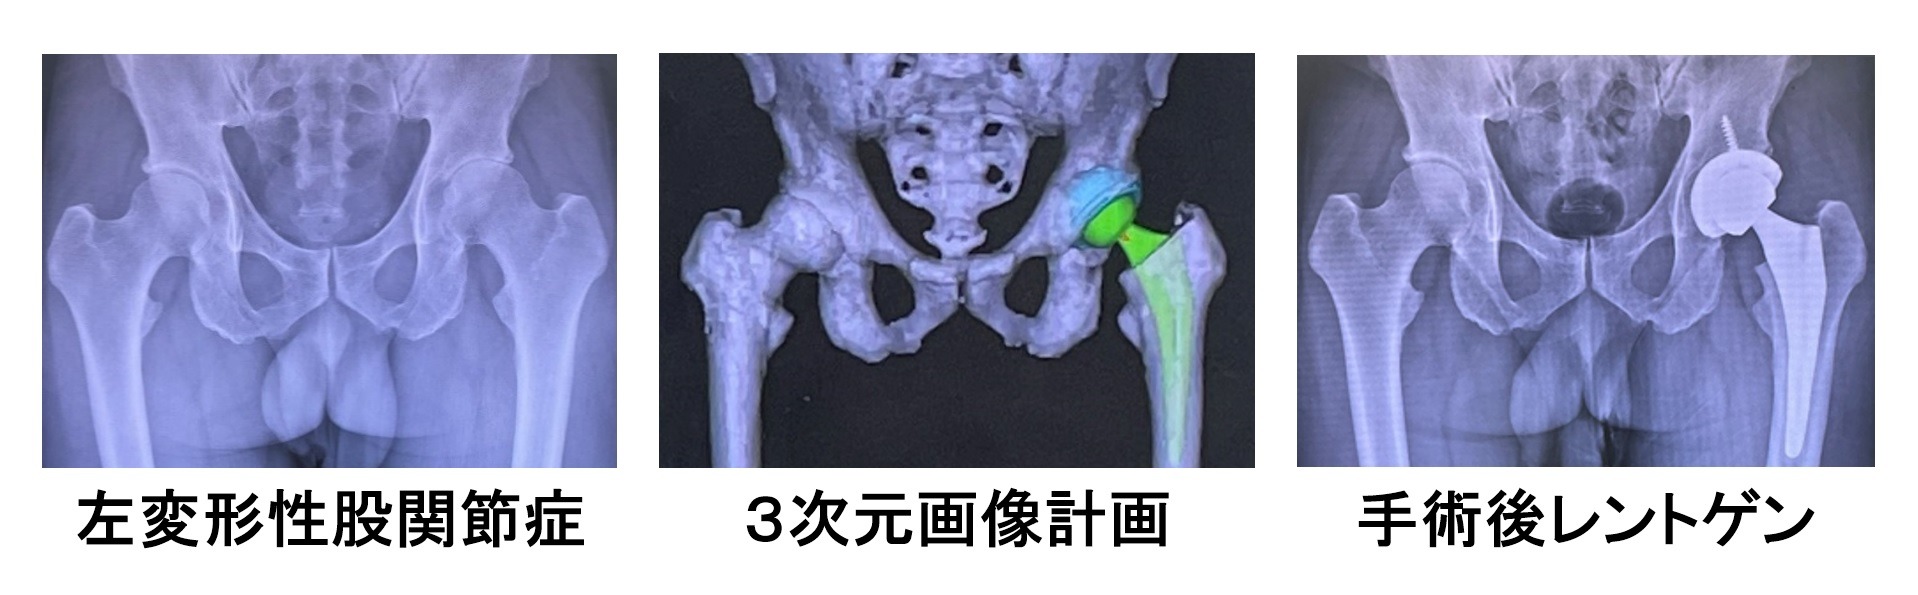

①CT画像を用いた三次元手術計画(LEXY社3次元術前計画支援ソフトを使用)を行います

患者さんごとに適切な人工関節の大きさ、形状、位置などを正確に決定することができます。

②当院ではCTナビゲーション手術(Stryker社CT-based Hip Navigation System)を行っております

CTによる手術計画どおりに人工関節を理想的位置に設置することで長期成績が期待できます。

なた、術後脱臼を予防でき、術後の脚長差も改善します。